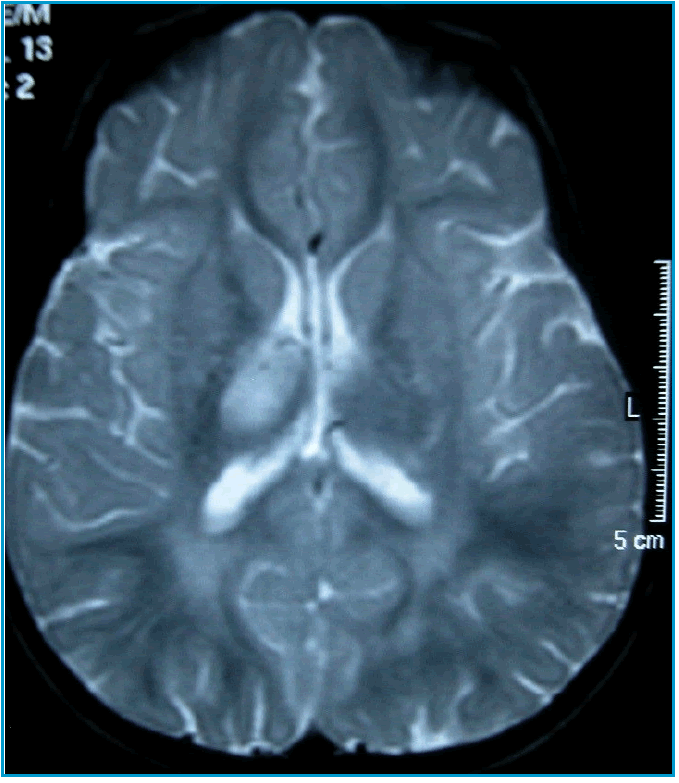

Fondamentale per la diagnosi è la RMN dell’encefalo e del midollo che mostra la presenza nelle sequenze T2-pesate di multiple aree iperintense che presentano caratteristicamente margini indistinti e assumono il mezzo di contrasto [4,5].

S., 2 anni, viene ricoverata per improvvisa comparsa di manifestazioni neurologiche (irritabilità, atassia, emiparesi, disestesia, strabismo) a breve distanza da un’infezione delle vie aeree superiori. Gli indici di flogosi sono negativi e l’esame del liquor evidenzia una modesta pleiocitosi linfocitaria con glicorrachia e proteinorrachia normali e assenza di bande oligoclonali. La RMN mostra multiple aree di iperintensità a livello dell’encefalo, in corrispondenza del talamo, del peduncolo cerebrale dx, dei gangli della base, del chiasma ottico e dei tratti ottici, e del midollo spinale, a livello di C3-C5, C7-D3, D7-D8 (Figure 1-3). Alcune delle aree captano in maniera disomogenea il gadolinio. Nel sospetto di ADEM la bambina viene trattata con boli di metilprednisolone e.v. (10 mg/Kg) per 5 giorni con rapido miglioramento dei segni neurologici. Il follow-up a 5 mesi documenta un’obiettività neurologica pressoché normale e una significativa riduzione delle aree iperintense, precedentemente rilevate, alla RMN.